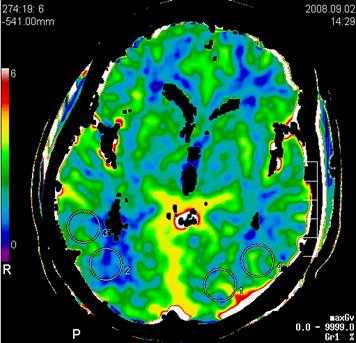

Пример: карта объема мозгового кровотока, с указанием показателей повышения плотности вещества головного мозга во время прохождения быстрого болюса контрастного вещества.

Основными параметрами являются: церебральный кровоток (ЦК), объем церебрального кровотока (ОЦК), среднее время транзита (СВТ) и время до максимума (ВМ).

2. Объем церебрального кровотока определяется как процентное содержание кровеносных сосудов в определённом объёме мозговой ткани. Поэтому высоковаскуляризированные области головного мозга типа подкорковых узлов или кортикальной поверхности имеют более высокие значения ОЦК по сравнению с менее васкуляризированным белым веществом головного мозга. Однако ОЦК является функциональным параметром и изменяется в зависимости от диаметра сосудов в контексте сосудистой ауторегуляции.

В отличие от ЦК, которое при ишемии имеет пониженное значение в ядре инфаркта и пенумбре, значение ОЦК в пенумбре обычно увеличивается. Это вызвано ауторегуляцией мозговых сосудов: уменьшение ЦК должно компенсироваться расширением соответствующих сосудов. И, наоборот, в необратимо повреждённом ядре инфаркта ауторегуляция обычно уже не действует, а значение ОЦК понижается. Это оказывает помощь в диагностике инсультов: области с пониженными значениями ОЦК в острой стадии ишемии являются, как правило, необратимо повреждёнными.

Пример: Пациент С, 52 лет, исследование перфузии мозгового кровотока, немедленное (до 3 часов с момента возникновения очаговой неврологической симптоматики в виде левостороннего гемипареза с элементами моторной афазии).

При проведении стандартного нативного исследования в первые 3 часа истинных признаков развившегося инфаркта (наличия гиподенсивной зоны некроза мозговой ткани, нарушения дифференцировки серого и бело вещества, наличия отека вещества головного мозга, и признаков окклюзии правой СМА) не отмечается.

Однако при проведении немедленной перфузии мозгового кровотока на основании карты объема мозгового кровотока, определяется наличие грубой зоны локальной аперфузии (отсутствия мозгового окруженной зоной гипоперфузии в правом полушарии на уровне базальных ганглиев в проекции височно - теменных отделов правого полушария в территориальном бассейне кровоснабжения правой средней мозговой артерии (правой СМА).